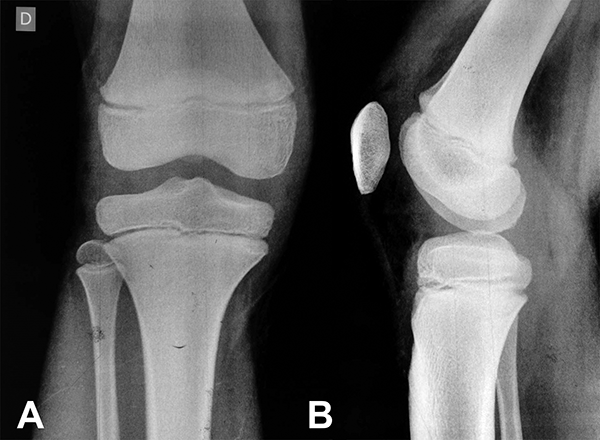

Figura 1: Rx de rodilla, fisis abiertas.

Figura 3: Miembros inferiores niño (contextura física pequeña).

En primer lugar, el fracaso precoz del injerto está asociado a su diámetro, así como a la edad del paciente. Se sabe que el diámetro de los isquiotibiales está directamente relacionado con la altura, el sexo y la contextura física; esto significa que en los niños la obtención de un autoinjerto con un diámetro adecuado para la reconstrucción del LCA puede ser todo un reto.